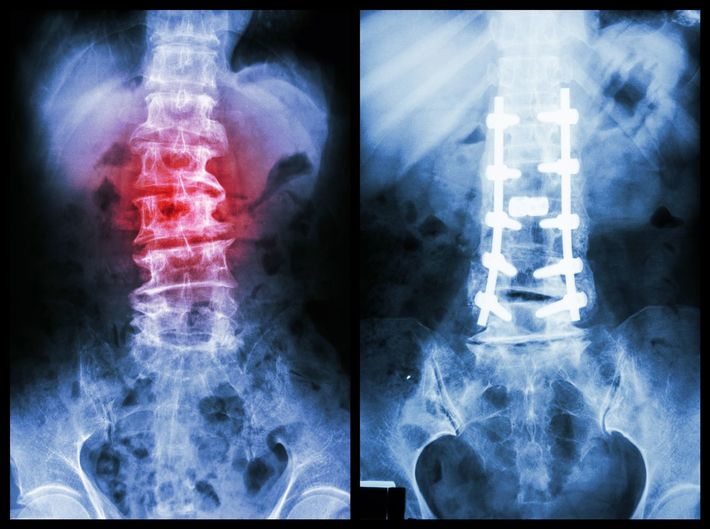

※写真はイメージです